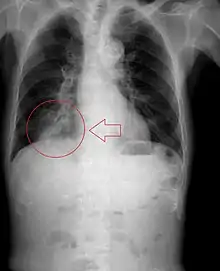

| Pulmonary aspiration | |

Pulmonary aspiration is the entry of material such as pharyngeal secretions, food or drink, or stomach contents from the oropharynx or gastrointestinal tract, into the larynx (voice box) and lower respiratory tract, the portions of the respiratory system from the trachea (windpipe) to the lungs. A person may inhale the material, or it may be delivered into the tracheobronchial tree during positive pressure ventilation. When pulmonary aspiration occurs during eating and drinking, the aspirated material is often colloquially referred to as "going down the wrong pipe".

Consequences of pulmonary aspiration range from no injury at all, to chemical pneumonitis or pneumonia, to death within minutes from asphyxiation. These consequences depend on the volume, chemical composition, particle size, and presence of infectious agents in the aspirated material, and on the underlying health status of the person.

In healthy people, aspiration of small quantities of material is common and rarely results in disease or injury. People with significant underlying disease or injury are at greater risk for developing respiratory complications following pulmonary aspiration, especially hospitalized patients, because of certain factors such as depressed level of consciousness and impaired airway defenses (gag reflex and respiratory tract antimicrobial defense system). The lumen of the right main bronchus is more vertical and slightly wider than that of the left, so aspirated material is more likely to end up in this bronchus or one of its subsequent bifurcations.